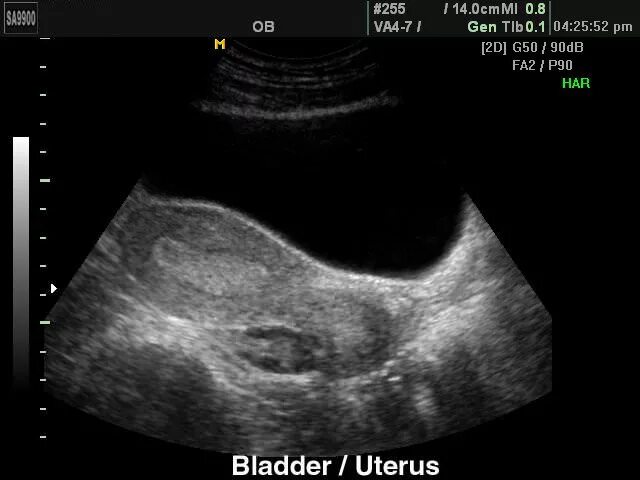

Узи при месячных